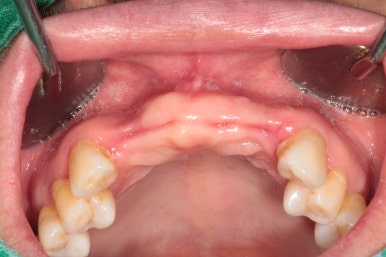

고개를 좌우로 돌려 좌측과 우측을 살펴보았습니다.

제가 앞에서 본다고 생각하시면, 왼쪽 사진이 우측이겠지요?

우측 가쪽 앞니 (측절치)에서 active하게 농양이 나오고 있는 것을 보실 수 있어요.

당연히 위턱 앞니들이 모두 흔들흔들 합니다.

어금니는 임플란트로 치료를 받으셨지만, 앞니는 틀니를 해야한다는 말에 치과 방문을 미루고 미루시다가 소문을 듣고 저희 치과를 방문해주신 경우였어요..!